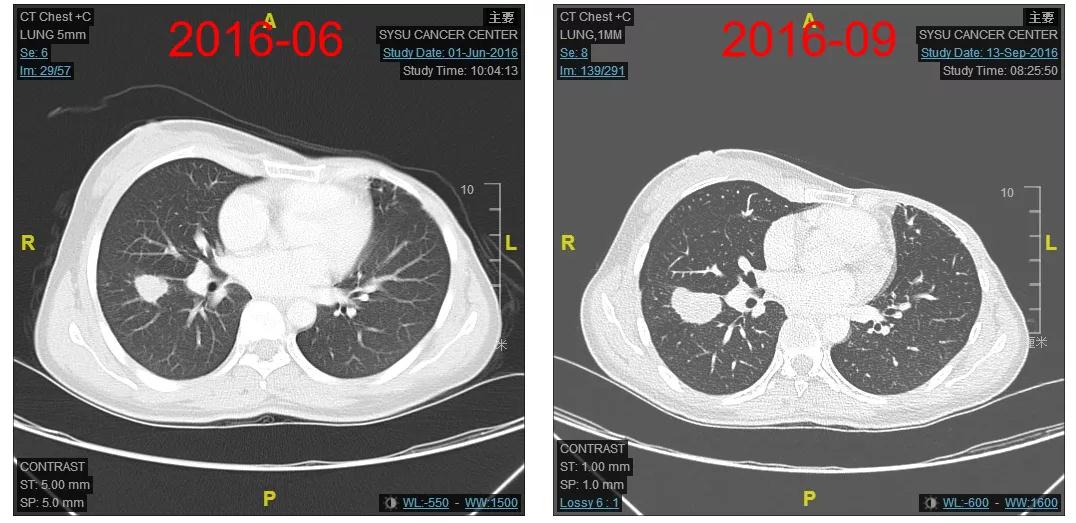

2016-06-01复查CT:右肺下叶上段团块状肿物(图1),考虑转移。

2016-07-07右肺组织穿刺活检病理:符合乳腺癌肺转移。免疫组化:ER(-),PR(-),HER2(3+),Ki-67(约40%+)。

2016-12-06开始使用T-DM1(恩美曲妥珠单抗)方案治疗,首次疗效评估PR,后续最佳疗效CR(图2-3)。

患者为初诊IIIC期的HER2阳性乳腺癌,单靶曲妥珠单抗辅助治疗过程中发生多发肺转移;治疗采用T-DM1治疗获得迅速缓解(CR),PFS已近5年;用药过程中主要毒性集中在肝酶升高、血小板下降及中性粒细胞下降,均为1-2度,可对症处理或自行缓解;T-DM1一线治疗方案耐受性好,生活质量无影响。